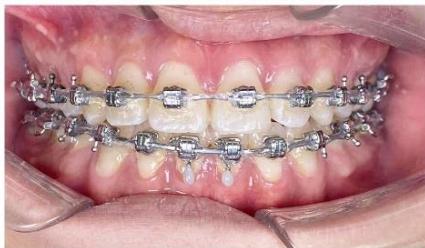

Figure 6: Canine retraction on a $0.019 \times 0.025$ -inch stainless steel archwire using sliding mechanics

During the canine retraction phase, the patient wore intermaxillary elastics (3/16-inch, 3.5 oz) from the maxillary first molars to the mandibular first and second premolars to stabilize posterior occlusal interdigitation, as canine retraction using sliding mechanics tends to generate rotational moments and increases the risk of posterior occlusal disclusion [6,7].

From the rigid archwire stage onward, an ART torque spring was placed in the mandibular four-incisor region and maintained continuously throughout the canine retraction phase. The ART appliance functioned as an auxiliary torque spring, generating active positive torque to direct the incisor roots into cancellous bone and counteract the negative torque moments produced during space closure with force application below the center of resistance [6,9]. Studies on periodontal tissue response have demonstrated that light and continuous torque forces facilitate safe alveolar bone remodeling, particularly in regions where the incisor roots are positioned close to the labial cortical plate [22,23].

Figure 7: Torque control of the mandibular incisor roots using an ART torque spring during space closure